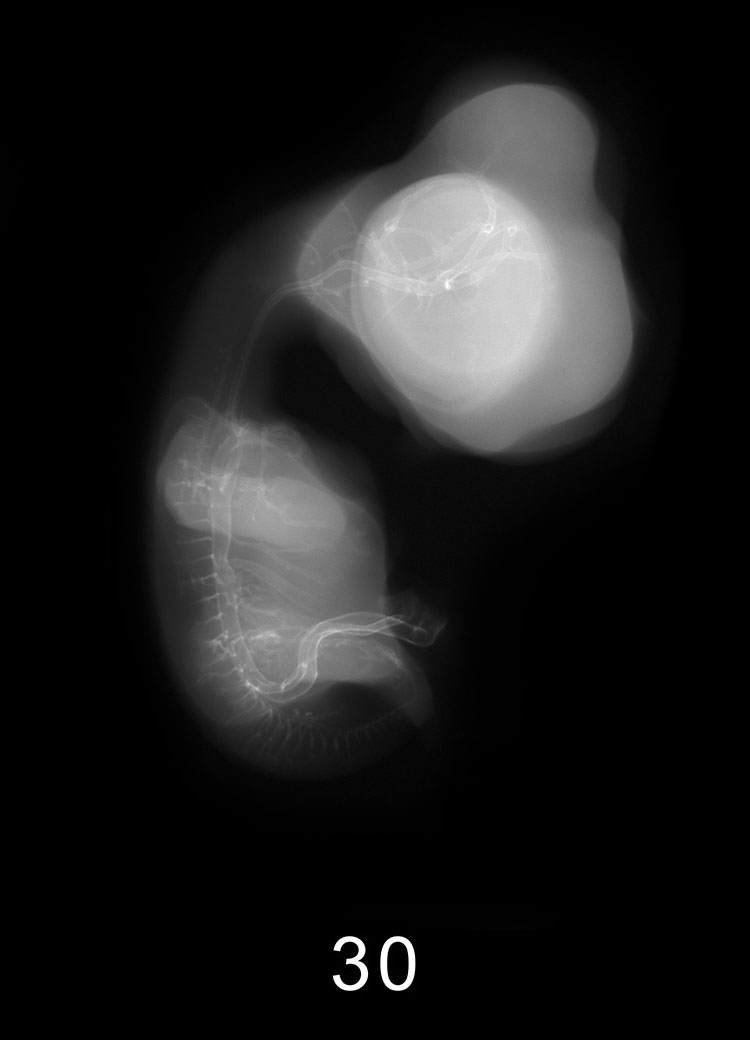

Chick Embryo Microangiography

Images listed by Hamburger-Hamilton (HH) Stage

Hamburger-Hamilton (HH) stages are a system used by those who study chick embryo development to describe the apparent maturity of the developing chick from laying of the egg to hatching. An embryo is assigned an HH stage (numbered from 1 to 46) based on its physical shape and visible features (morphology). This staging system is not dependent on the chronological age nor the size of the embryo, which are susceptible to variations due to breed, temperature during incubation, season, and time between egg laying and incubation. The stages, are in a sense, arbitrary levels of maturity based on multiple physical features. For example, embryos that might have different ages or sizes might be assigned the same HH stage based on their external appearance due to the natural variation which occurs between individuals or due to differing conditions during incubation.